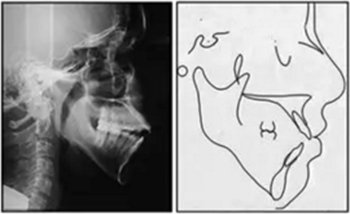

X片示:垂直向生長過度,下頜后縮、上頜前突,上切牙前傾、前突,下切牙前突但唇舌向傾角正常;雙側(cè)髁突畸形,提示退行性變。

影像學(xué):全景片示:牙根平行度可。頭顱側(cè)位片及疊加圖示:下頜骨發(fā)生逆時(shí)針旋轉(zhuǎn),面部輪廓改善;上切牙轉(zhuǎn)矩正常,下切牙輕微舌傾;唇突度減小,鼻唇角增大。